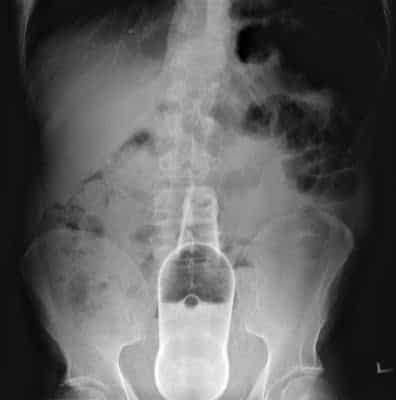

Un cop efectuades les proves mèdiques, el personal sanitari que va atendre aquesta persona va determinar que el mal en qüestió es generava a causa de la presència d'un cos estrany, el qual va resultar ser una ampolla d'oli d'oliva verge extra de 250 ml.

*La imatge de la notícia és una rèplica, ja que per protecció de dades i intimitat del pacient, aquesta no pot ser pública.